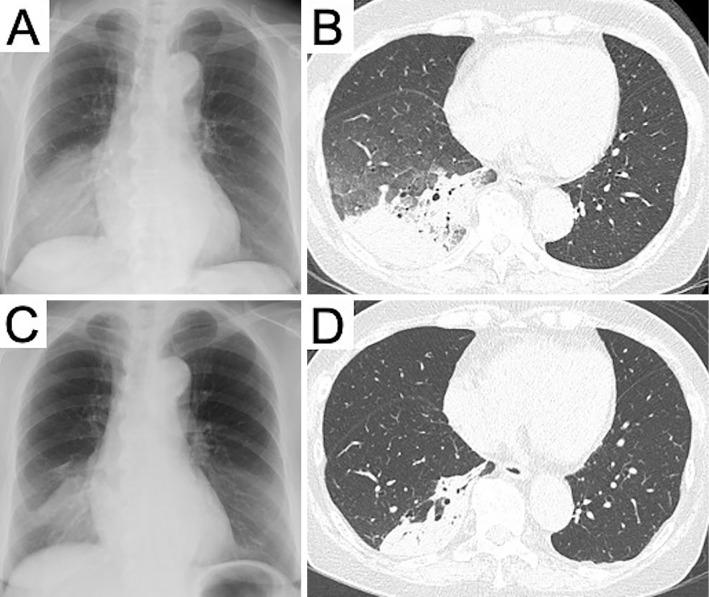

A 77-year-old woman with seronegative rheumatoid arthritis who was being treated with prednisolone (8 mg/day) and methotrexate (12 mg/week) visited our hospital with an 11-day history of a fever and dyspnea. Chest computed tomography showed infiltration in the right lower lobe. A transbronchial lung cryobiopsy (TBLC) showed cryptococcal cells, and bronchoalveolar lavage fluid later showed growth of Cryptococcus neoformans. She was treated with amphotericin B and flucytosine for about four weeks, and the pulmonary shadows improved. The treatment was then changed to fluconazole as outpatient consolidation and maintenance therapy. A rare case of pulmonary cryptococcosis diagnosed by a TBLC is reported.

一位 77 岁的女性,患有血清阴性类风湿关节炎,正在接受泼尼松龙(8 毫克/天)和甲氨蝶呤(12 毫克/周)治疗,因发热和呼吸困难来我院就诊,病史 11 天。胸部计算机断层扫描显示右下叶浸润。经支气管镜肺冷冻活检(TBLC)显示隐球菌细胞,支气管肺泡灌洗液随后显示新型隐球菌生长。她接受了大约四周的两性霉素 B 和氟胞嘧啶治疗,肺部阴影有所改善。然后改为氟康唑作为门诊巩固和维持治疗。报告了一例经 TBLC 诊断的罕见肺隐球菌病。